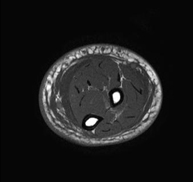

- RM Rodilla

Exploración para el estudio de lesiones en la articulación, como roturas meniscales y de ligamentos cruzados (unicamente detectables mediante esta prueba), condropatía o desgaste del cartílago y multitud de otras alteraciones derivadas de la actividad deportiva y los cambios degenerativos (osteoartrosis). Tiene una duración aproximada de 18 minutos. No emplea radiación ionizante.